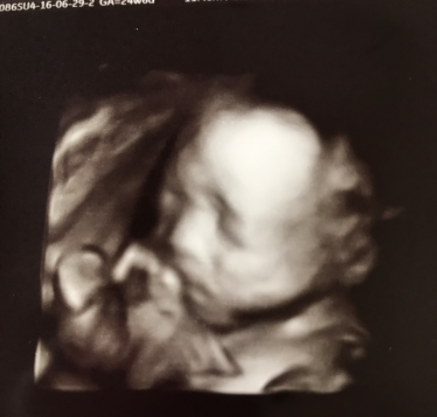

24週3日(24w3d・男の子)|saachi さん(26歳)

エコー写真撮影時のエピソード:

妊娠初期に受けて以来の久しぶりの4Dエコー。赤ちゃんのお顔がはっきり見えてとてもうれしかったけど、赤ちゃんはとっても迷惑そうなお顔。そのままグルンと回ってしまって背中を向けられました。

実は、このとき、胎児スクリーニングをしてまして、お腹にプローブを強く押し当てられ気分が悪くなっていたのです。赤ちゃんのおかげで検査は中止に。

赤ちゃんが守ってくれたような気持ちになって、検査ができず残念なような、うれしいような気分になりました。